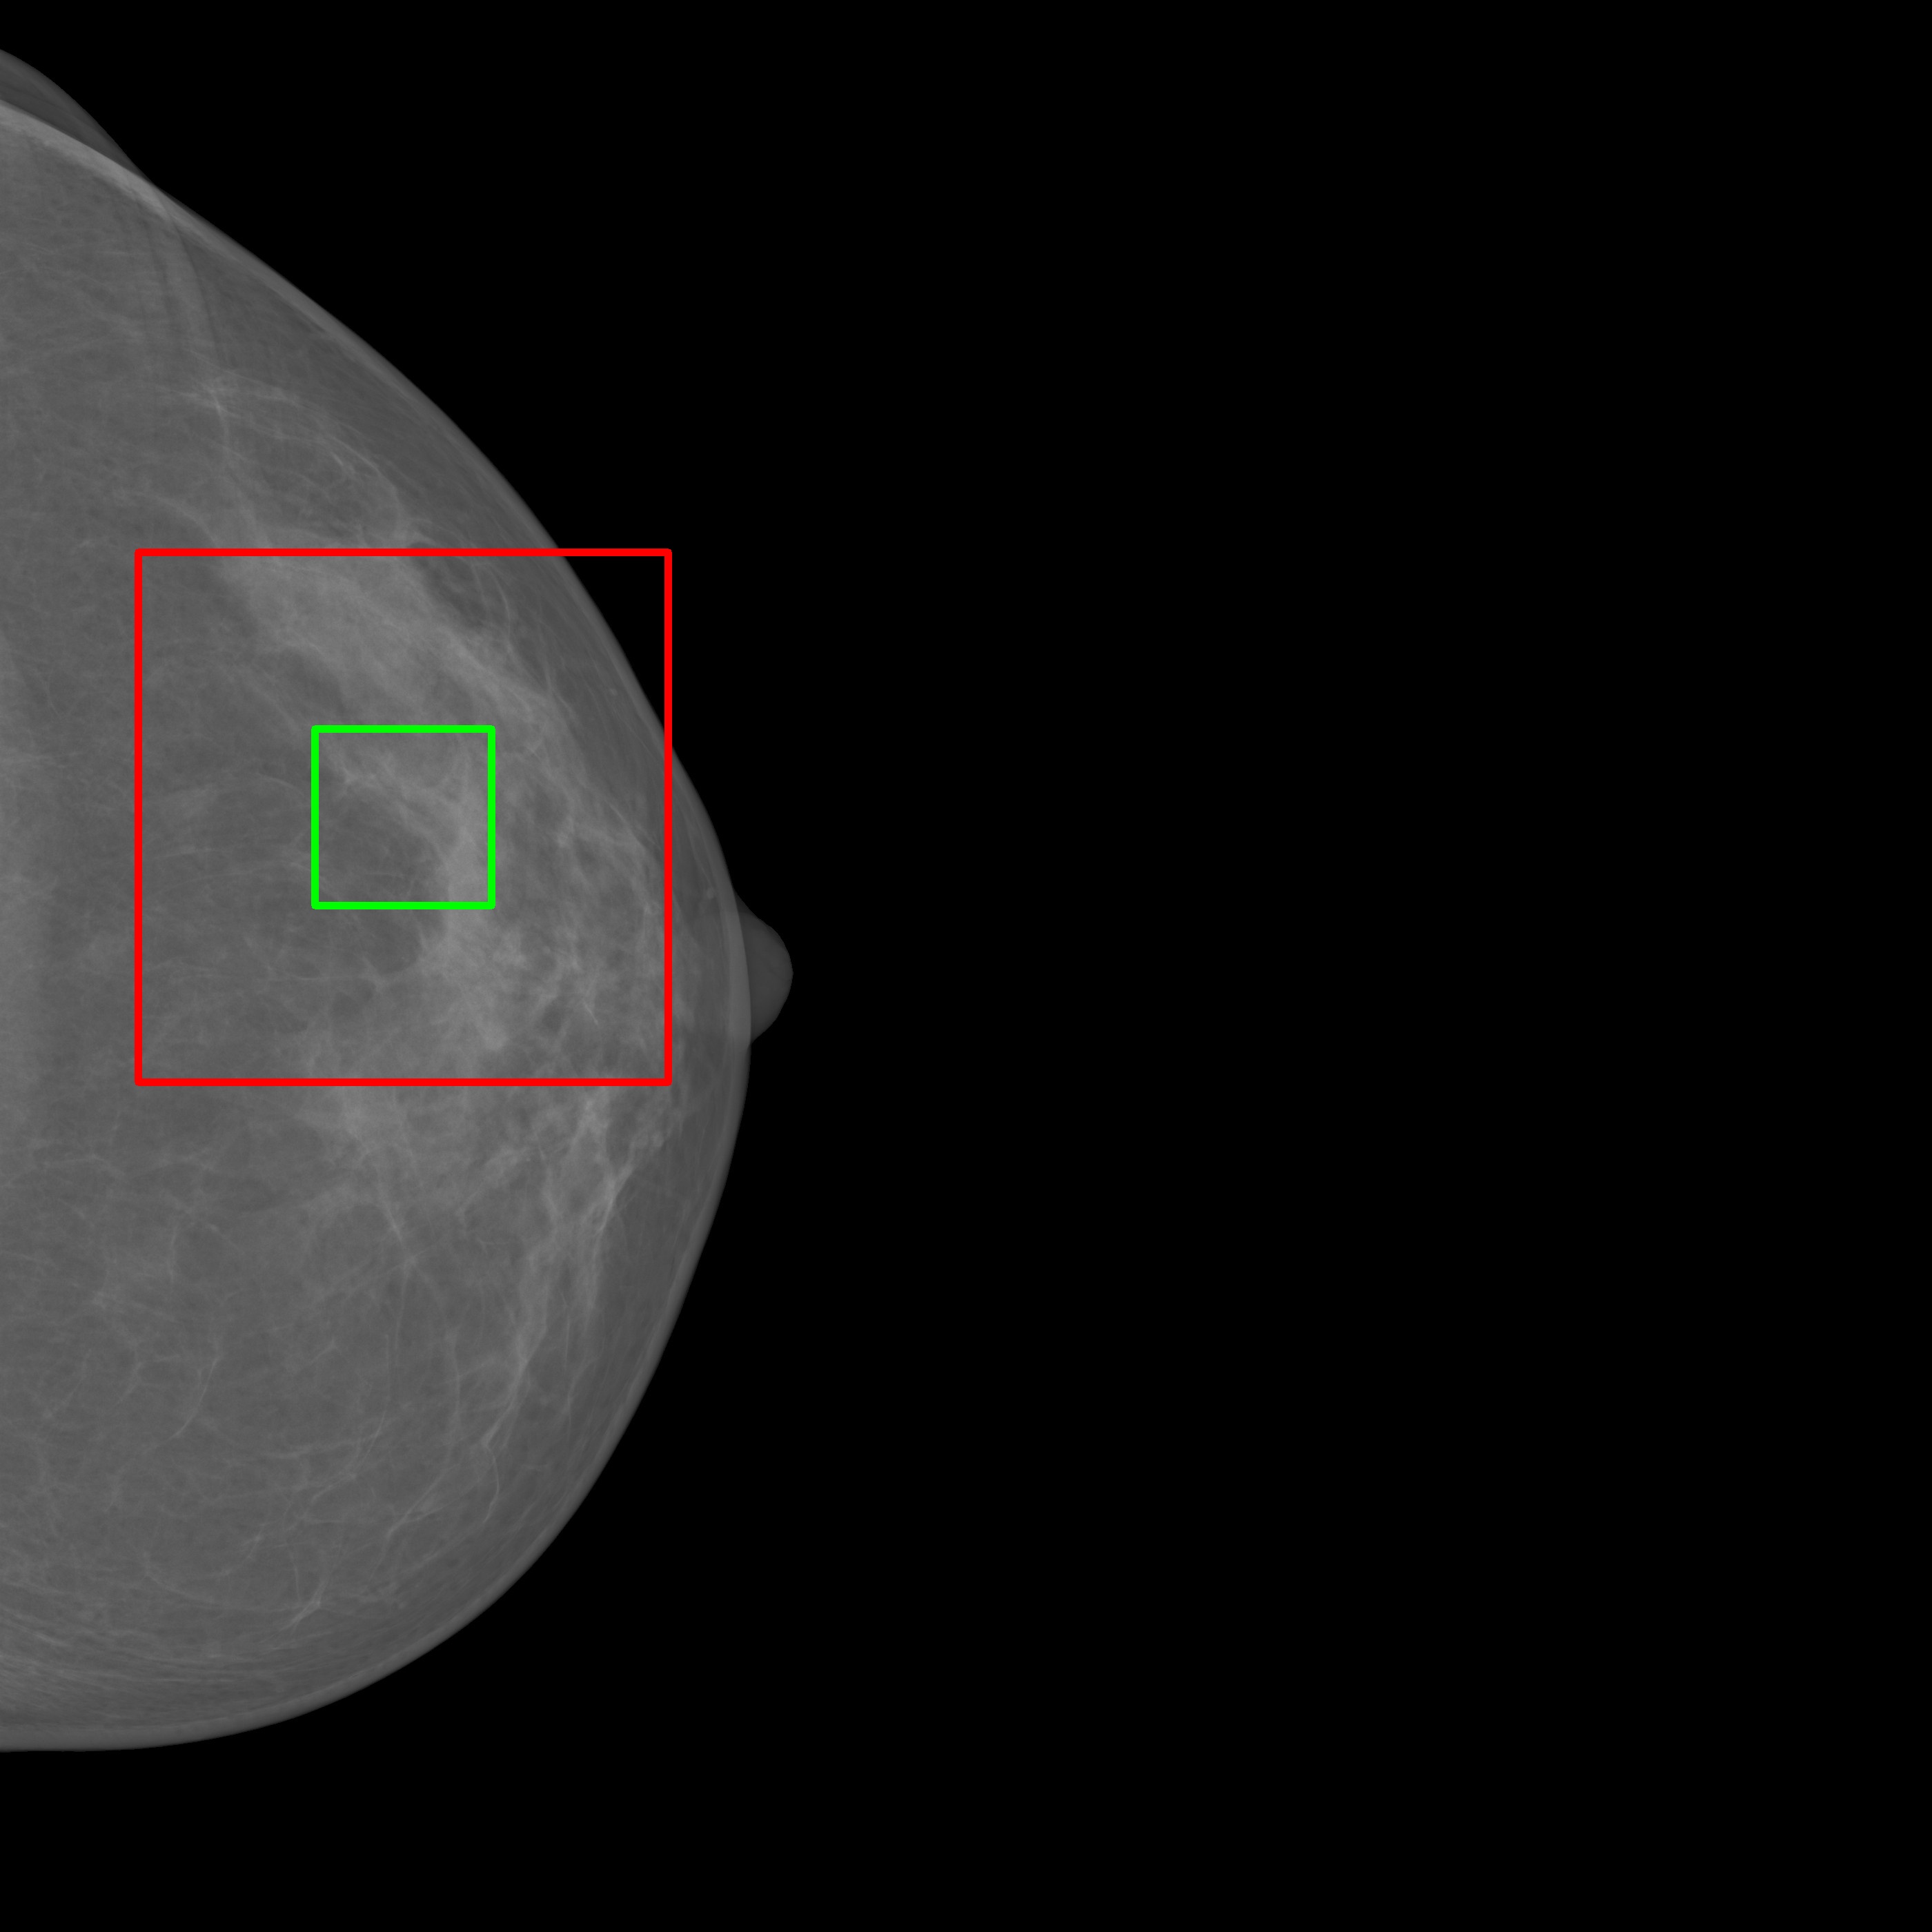

To assess potential memorization, synthetic images produced by MAMBO were compared against real images from the training dataset to identify any significant visual overlap or unintended reproduction. Top-k nearest neighbors were retrieved using cosine similarity in the Mammo-CLIP embedding space [8]. As shown in Fig. 5, even when embedding similarity is high, the generated images differ clearly from the originals in shape, tissue structure, and texture. This indicates that MAMBO’s outputs reflect genuine generalization, not memorization or data leakage.

4.6 Anomaly Segmentation

The InBreast dataset was used to evaluate the anomaly segmentation performance. The evaluation scenario is basically zero-shot, as the images tested on are different from those used to train MAMBO on. To allow comparison with existing approaches used in the domain of radiology, only the low-resolution (global context) model was used as described in Sec. 3 and trained on the subset of healthy images taken from the VinDr dataset.

To select the optimal value of the timestep parameter () for the anomaly segmentation task, values in the range were evaluated. The optimal value of , was obtained for all masses in the dataset, corresponding to an IoU of 0.216.

To further probe the capabilities of recognizing lesions of different sizes, Tab. 6 illustrates the performance of MAMBO using the optimal . To produce the data, lesions are grouped in buckets according to size. The size of lesions (in pixels) in the dataset follows an exponential distribution. Lesions are assigned to the buckets using a logarithmic scale, which yields buckets with the same number of images (18) in each, except for the last bucket, which contains 17 images.

| Area (px) | 64 | 128 | 222 | 521 | 951 | 2187 |

|---|---|---|---|---|---|---|

| IoU | 0.019 | 0.069 | 0.125 | 0.280 | 0.423 | 0.393 |

| Area is represented on a log scale, median size is shown for each bucket. | ||||||

As Tab. 6 shows, larger lesions are easier to detect using the model. Exceptions occur when a lesion grows large, nearing breast size, and the model finds it difficult to remove the whole anomaly. Quantitatively, the best result achieved by the proposed approach is as high as , a significant improvement over the reported for AnoDDPM in [44] for brain radiology images.